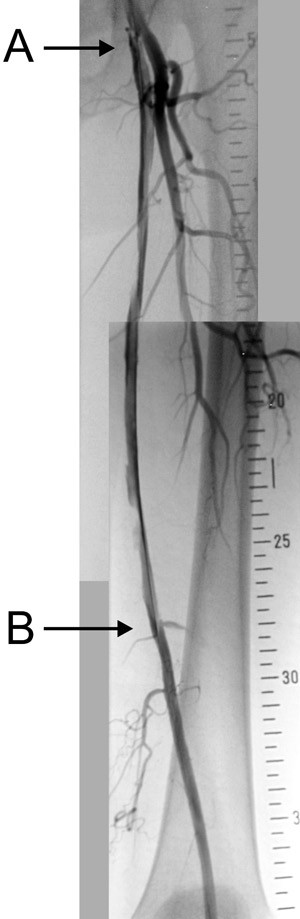

Med denne teknikken søker man med ledesonden aktivt å gå inn i åreveggen forbi det okkluderte området. Ballongdilatasjon i det subintimale rom lager en «falsk» kanal (fig 1b). Teknikken egner seg både for korte og lange okklusjoner og er et reelt alternativ til operativ behandling (fig 2). Metoden er lite egnet ved svært forkalkede arterier. Rekanalisering lykkes i cirka 80 % av tilfellene, men resultatene varierer mellom ulike sentre og er avhengig av sykdommens alvorlighetsgrad. Ved Oslo universitetssykehus, Aker har vi i en studie av pasienter med lange okklusjoner i lårarterien sett at hos 64 % av pasientene var den subintimale kanalen fortsatt åpen etter fem år (10). Dette er sammenliknbart med resultatene etter åpen kirurgi.

Femoropoliteal bypass er det vanligste kirurgiske inngrepet ved okklusjoner av lårarterien. Korte bypasser gir bedre resultater enn lengre (17). Hvis a. popliteas kvalitet tillater det, avslutter man helst en bypass ovenfor kneet, slik at bypassen ikke blir utsatt for de ytre påkjenninger som bevegelse av kneet medfører (fig 3).